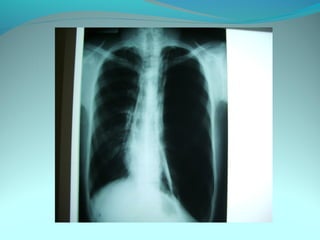

Clarté retroclaviculaire gauche d 3cm de diam

entouré d’une paroi de 1cm d’epaisseur

La limite interne se confend avec le mediastin

Les autre limites sont nette

DIAGNOSTIC

Caverne tuberculeuse gauche